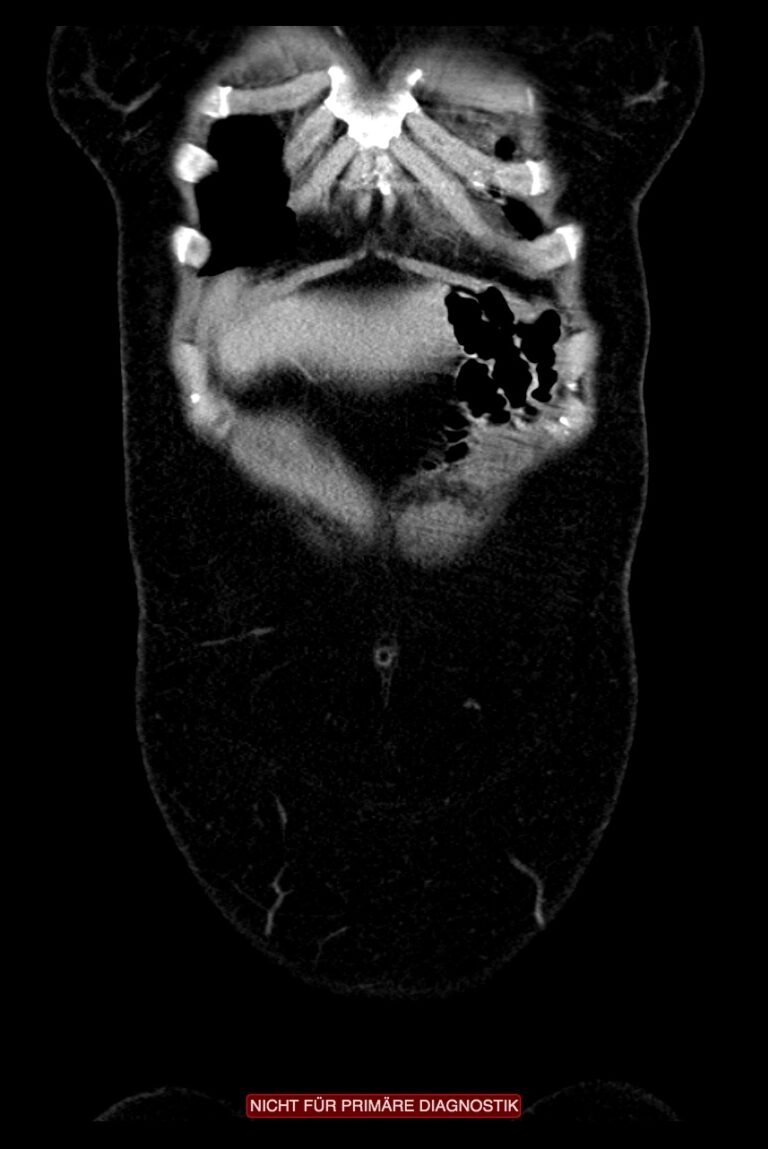

Thoraxmagen

Die Maximalvariante einer paraösophagealen Hernie ist der Thoraxmagen. Dabei rutscht ein Teil oder der gesamte Magen durch den Zwerchfellbruch in den Thorax. Man spricht auch vom “upside-down-stomach”. Das Beschwerdebild der Patienten ist durch thorakale Enge, Druckgefühl, Dysphagie und Atemnot geprägt. Unbehandelt kann sich die Situation zu einem noch extremeren Befund ausweiten, dem Enterothorax, bei dem neben dem Magen auch andere abdominelle Organe wie z.B. das Kolon in den Brustkorb rutschen.

Hier sehen Sie einen Thoraxmagen in der Durchleuchtung. Deutlich zu sehen ist die Magenblase, die über dem Zwerchfell im Thorax zu Liegen kommt. Die Patienten berichtet über ein retrosternales Druckgefühl, Dysphagie, Regurgitationen und zunehmende Atemnot. Unbehandelt kann sich der Befund zum sog. Enterothorax ausweiten. Dabei rutschen weitere Anteile des Intestinums in den Thorax.